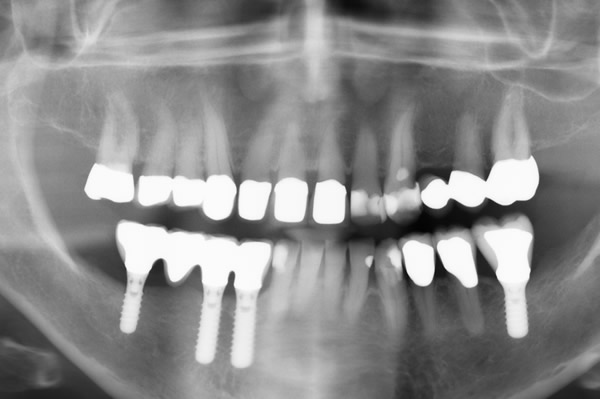

Digitales Röntgen

In unserer Praxis werden ausschließlich digitale Röntgenbilder erstellt.

Moderne digitale Röntgentechnik stellt eine Weiterentwicklung der herkömmlichen analogen Systeme dar.